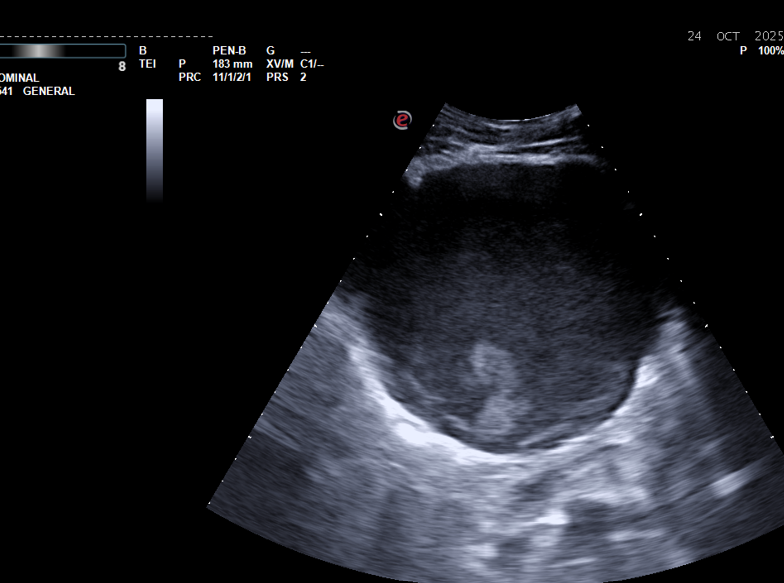

Realizamos ecografía abdominal en centro de salud, objetivándose grandes masas abdominales, no vascularizadas, de contenido hipoecogénico y heterogéneo, en todo el abdomen, sin distinguir si dependencia hepática o pancreática con leve dilatación de vía biliar intrahepática, vía extrahepática normal.

En ingreso realizan pruebas de imagen más específicas y visualizan quistes de gran tamaño similares a estudios previos, pero con dilatación de vía biliar intrahepática; confirmando obstrucción biliar intrahepática secundaria a compresión extrínseca por los quistes, con hepatomegalia, indicando drenaje percutáneo ecoguiado, con resolución del cuadro.